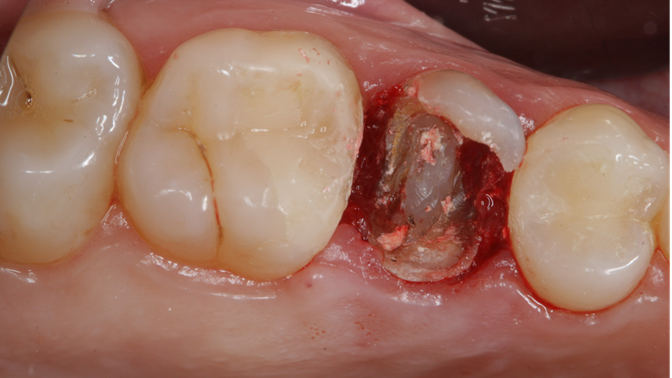

Clinical case: Extraction, immediate implant placement, & provisionalization

- Courtesy of Dr. Iulian Filipov, Romania -

AnyRidge, R2GATE, guided surgery, immediate placement, immediate provisionalization, initial stability, Dr. Iulian Filipov, #25, maxillary posterior, immediate loading, Mega ISQ

Products: